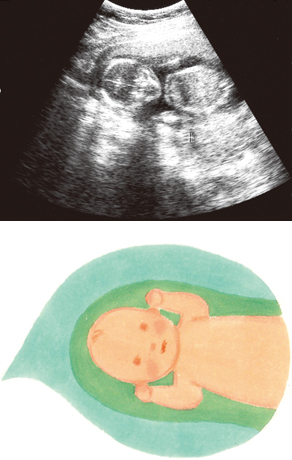

妊娠15週ころの超音波写真

ついに胎盤の基本構造が完成します。手足の骨や筋肉の成長が進み、羊水量も増えてくるので、赤ちゃんの動きは活発に。両腕を上に伸ばして、バンザイに見えるような人間らしいしぐさも発見。